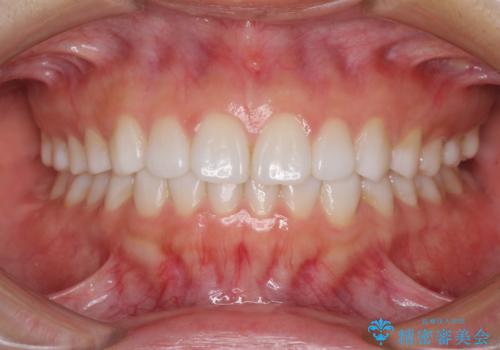

咬合平面の乱れを改善(全顎矯正歯科治療)

治療途中で体調を崩してしまったため、インプラント治療からブリッジによる補綴治療へ切り替え、矯正治療も早めの1年で装置を外しました。

下に降りていた左上の大臼歯が本来の位置に動き、かみ合わせが大変安定し、患者様には大変満足していただけました。